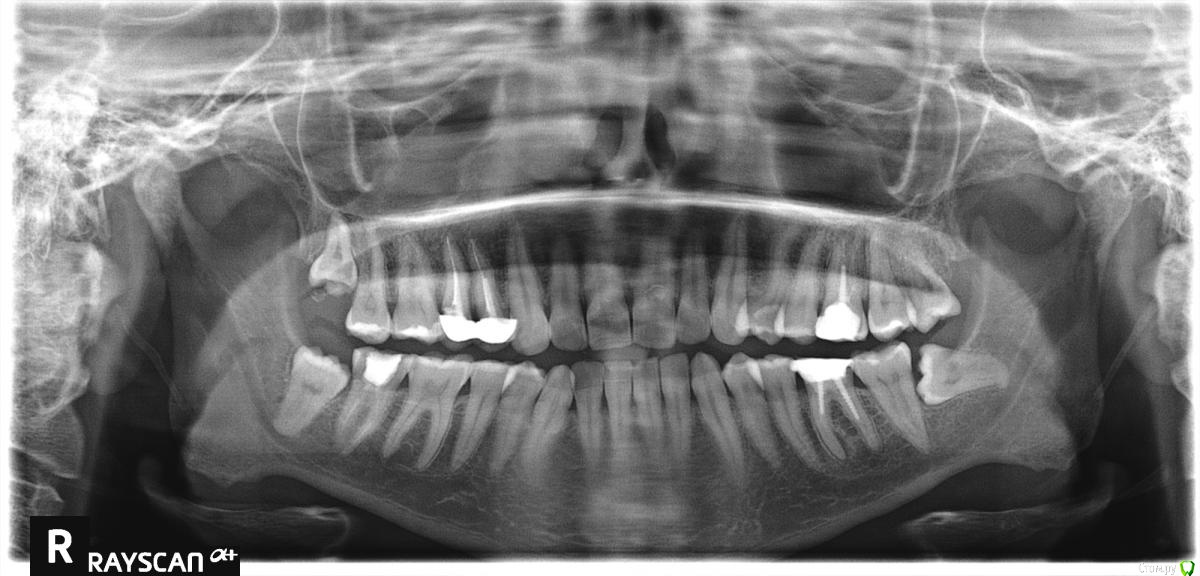

DariaL Опубликовано 14 сентября, 2020 Поделиться Опубликовано 14 сентября, 2020 (изменено) Добрый день! Подскажите, пожалуйста, обязательно ли удалять в моем случае зубы мудрости? Снимок прилагаю. Они не беспокоят.Планирую установить брекеты, так как повышена стираемость зубов из-за немного неправильного прикуса. Перед установкой брекетов всегда ли обязательно удаление зубов мудрости? А в моем случае?Врач сказал, что зуб мудрости на левой стороне (горизонтальный) пролегает рядом с нервом и есть вероятность его зацепить и навсегда остаться с онемевшей левой стороной лица. Это верно? Поможет ли ультразвуковое удаление избежать таких ужасных последствий? Изменено 14 сентября, 2020 пользователем DariaL Ссылка на комментарий

Irouil Опубликовано 14 сентября, 2020 Поделиться Опубликовано 14 сентября, 2020 Удалять надо даже если брекеты не планируются Риски повредить стенки нижнечелюстного канала (и находящийся в нем сосудисто-нервный пучок, соответственно) минимальны, но подробнее это понять можно по 3-х мерному снимку (компьютерная томография) В Вашем конкретном случае использование ультразвукового скальпеля практически никак на эти риски не повлияет 2 Ссылка на комментарий

Марья Моревна Опубликовано 14 сентября, 2020 Поделиться Опубликовано 14 сентября, 2020 В Вашем случае удалять надо.Сделайте КЛКТ. Скорее всего, всё не так страшно.Там для извлечения зуба так глубоко лезть и не нужно. А доктор, который Вас напугал, не имеет специзации по хирургии. 1 Ссылка на комментарий

Irouil Опубликовано 14 сентября, 2020 Поделиться Опубликовано 14 сентября, 2020 Я правильно понимаю, что удалять нужно все 4 зуба мудрости? ДаДействительно ли удаление ультразвуковым скальпелем намного менее травматично? Когда нужно проводить обширную остеотомию (пилить кость) - да, но это не Ваш случайОчень интересно узнать почему стоимость удаления ультразвуком настолько разная: от 13 до 45 тыс. рублей (Москва). Мы не обсуждаем здесь вопросы стоимости лечения 3 Ссылка на комментарий

Bier Опубликовано 15 сентября, 2020 Поделиться Опубликовано 15 сентября, 2020 удалять нужно, в ультразвуке большого смысла нет Ссылка на комментарий